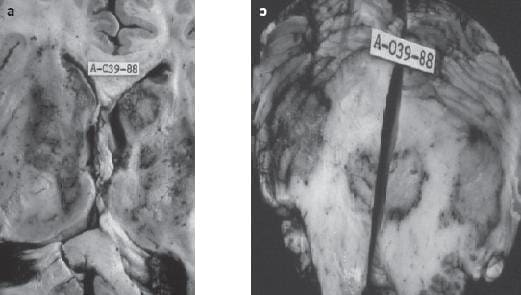

a. Virus: Citomegalovirus, el que más ha cambiado su comportamiento desde la aparición del VIH (fi g 1 a y b), Papovavirus (cuya asociación más conocida es con la leucoencefalopatía multifocal progresiva), Herpes simplex, que exige aun mayor observación en cuanto a su relación con SIDA.

Figura 1. a) Lesión destructiva muy extensa que compromete substancia blanca y corteza cerebral causada por el virus de inclusión citomegálica en paciente fallecido por VIH-SIDA (cortesía de JH García (q.e.p.d). b) El virus de inclusión citomegálica tiene características bien defi nidas que se reconocen claramente en la tinción de H &E 1.000 x aprox.